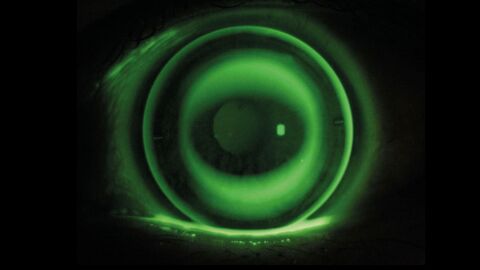

Studie: Sklerallinsen senken oxidativen Stress bei Keratokonus

Forschende aus Indien fanden heraus, dass Sklerallinsen bei Keratokonus den oxidativen Stress im Auge deutlich reduzieren. Schon nach sechs Stunden Tragezeit und besonders nach einem Monat sanken die ROS-Werte, während Sehschärfe und Augenbeschwerden sich spürbar verbesserten. Die Ergebnisse legen nahe, dass Sklerallinsen nicht nur Sehprobleme korrigieren, sondern möglicherweise auch die Krankheitsprogression bremsen könnten.